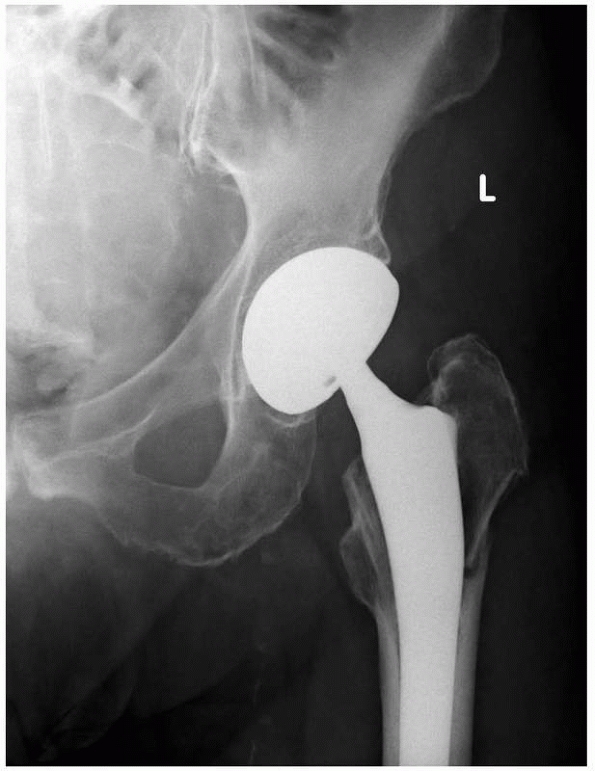

fixation of fractures after World War II centered on femoral diaphyseal

fractures. Intramedullary nailing gradually grew more popular

essentially superceded traction as the treatment of choice for femoral

fractures in the 1970s and 1980s, but traction is still used in parts

of the world and surgeons should understand the rationale behind its

use and its complications. In addition to the treatment of femoral

diaphyseal fractures, traction was used to treat acetabular fractures

and fracture dislocations of the hip as well as comminuted fractures of

the tibial diaphysis and distal tibia, although its role in the

management of these fractures is now extremely limited and essentially

confined to situations when internal and external fixation techniques

are unavailable. It is still used for the acute management of cervical

spine fractures.